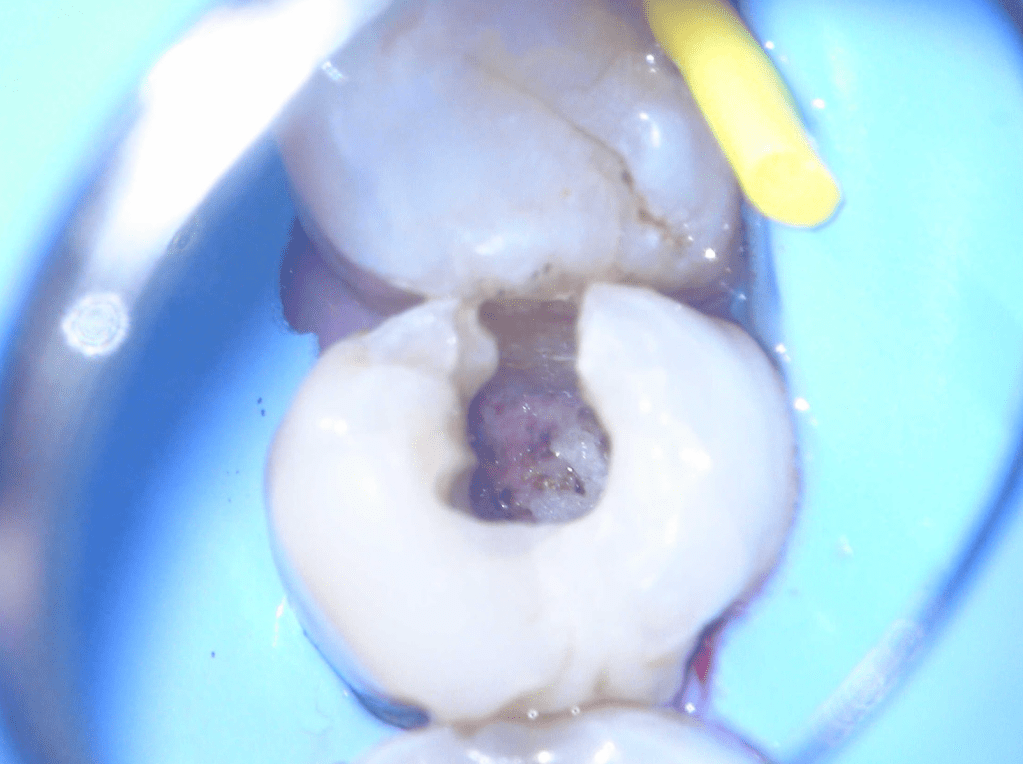

Gingivectomía + pulpotomía biodentine + reconstrucción

Pulpotomía biodentine + reco preendio

Pulpotomías